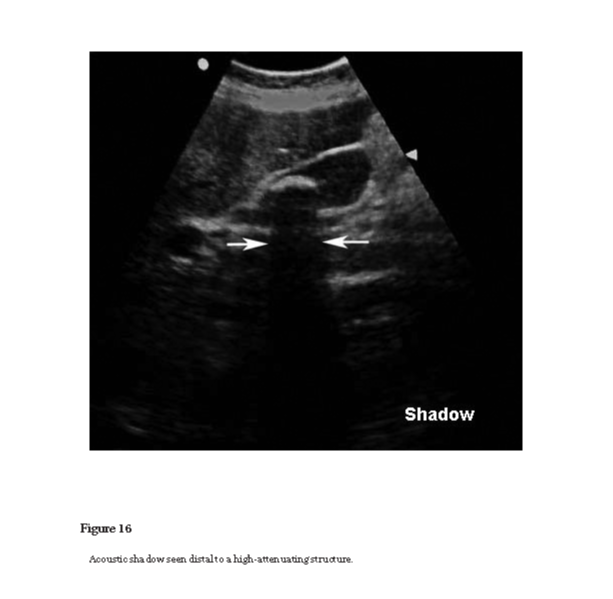

ultrasonic shadow

See acoustic shadow (see Figure 16).

Figure 16